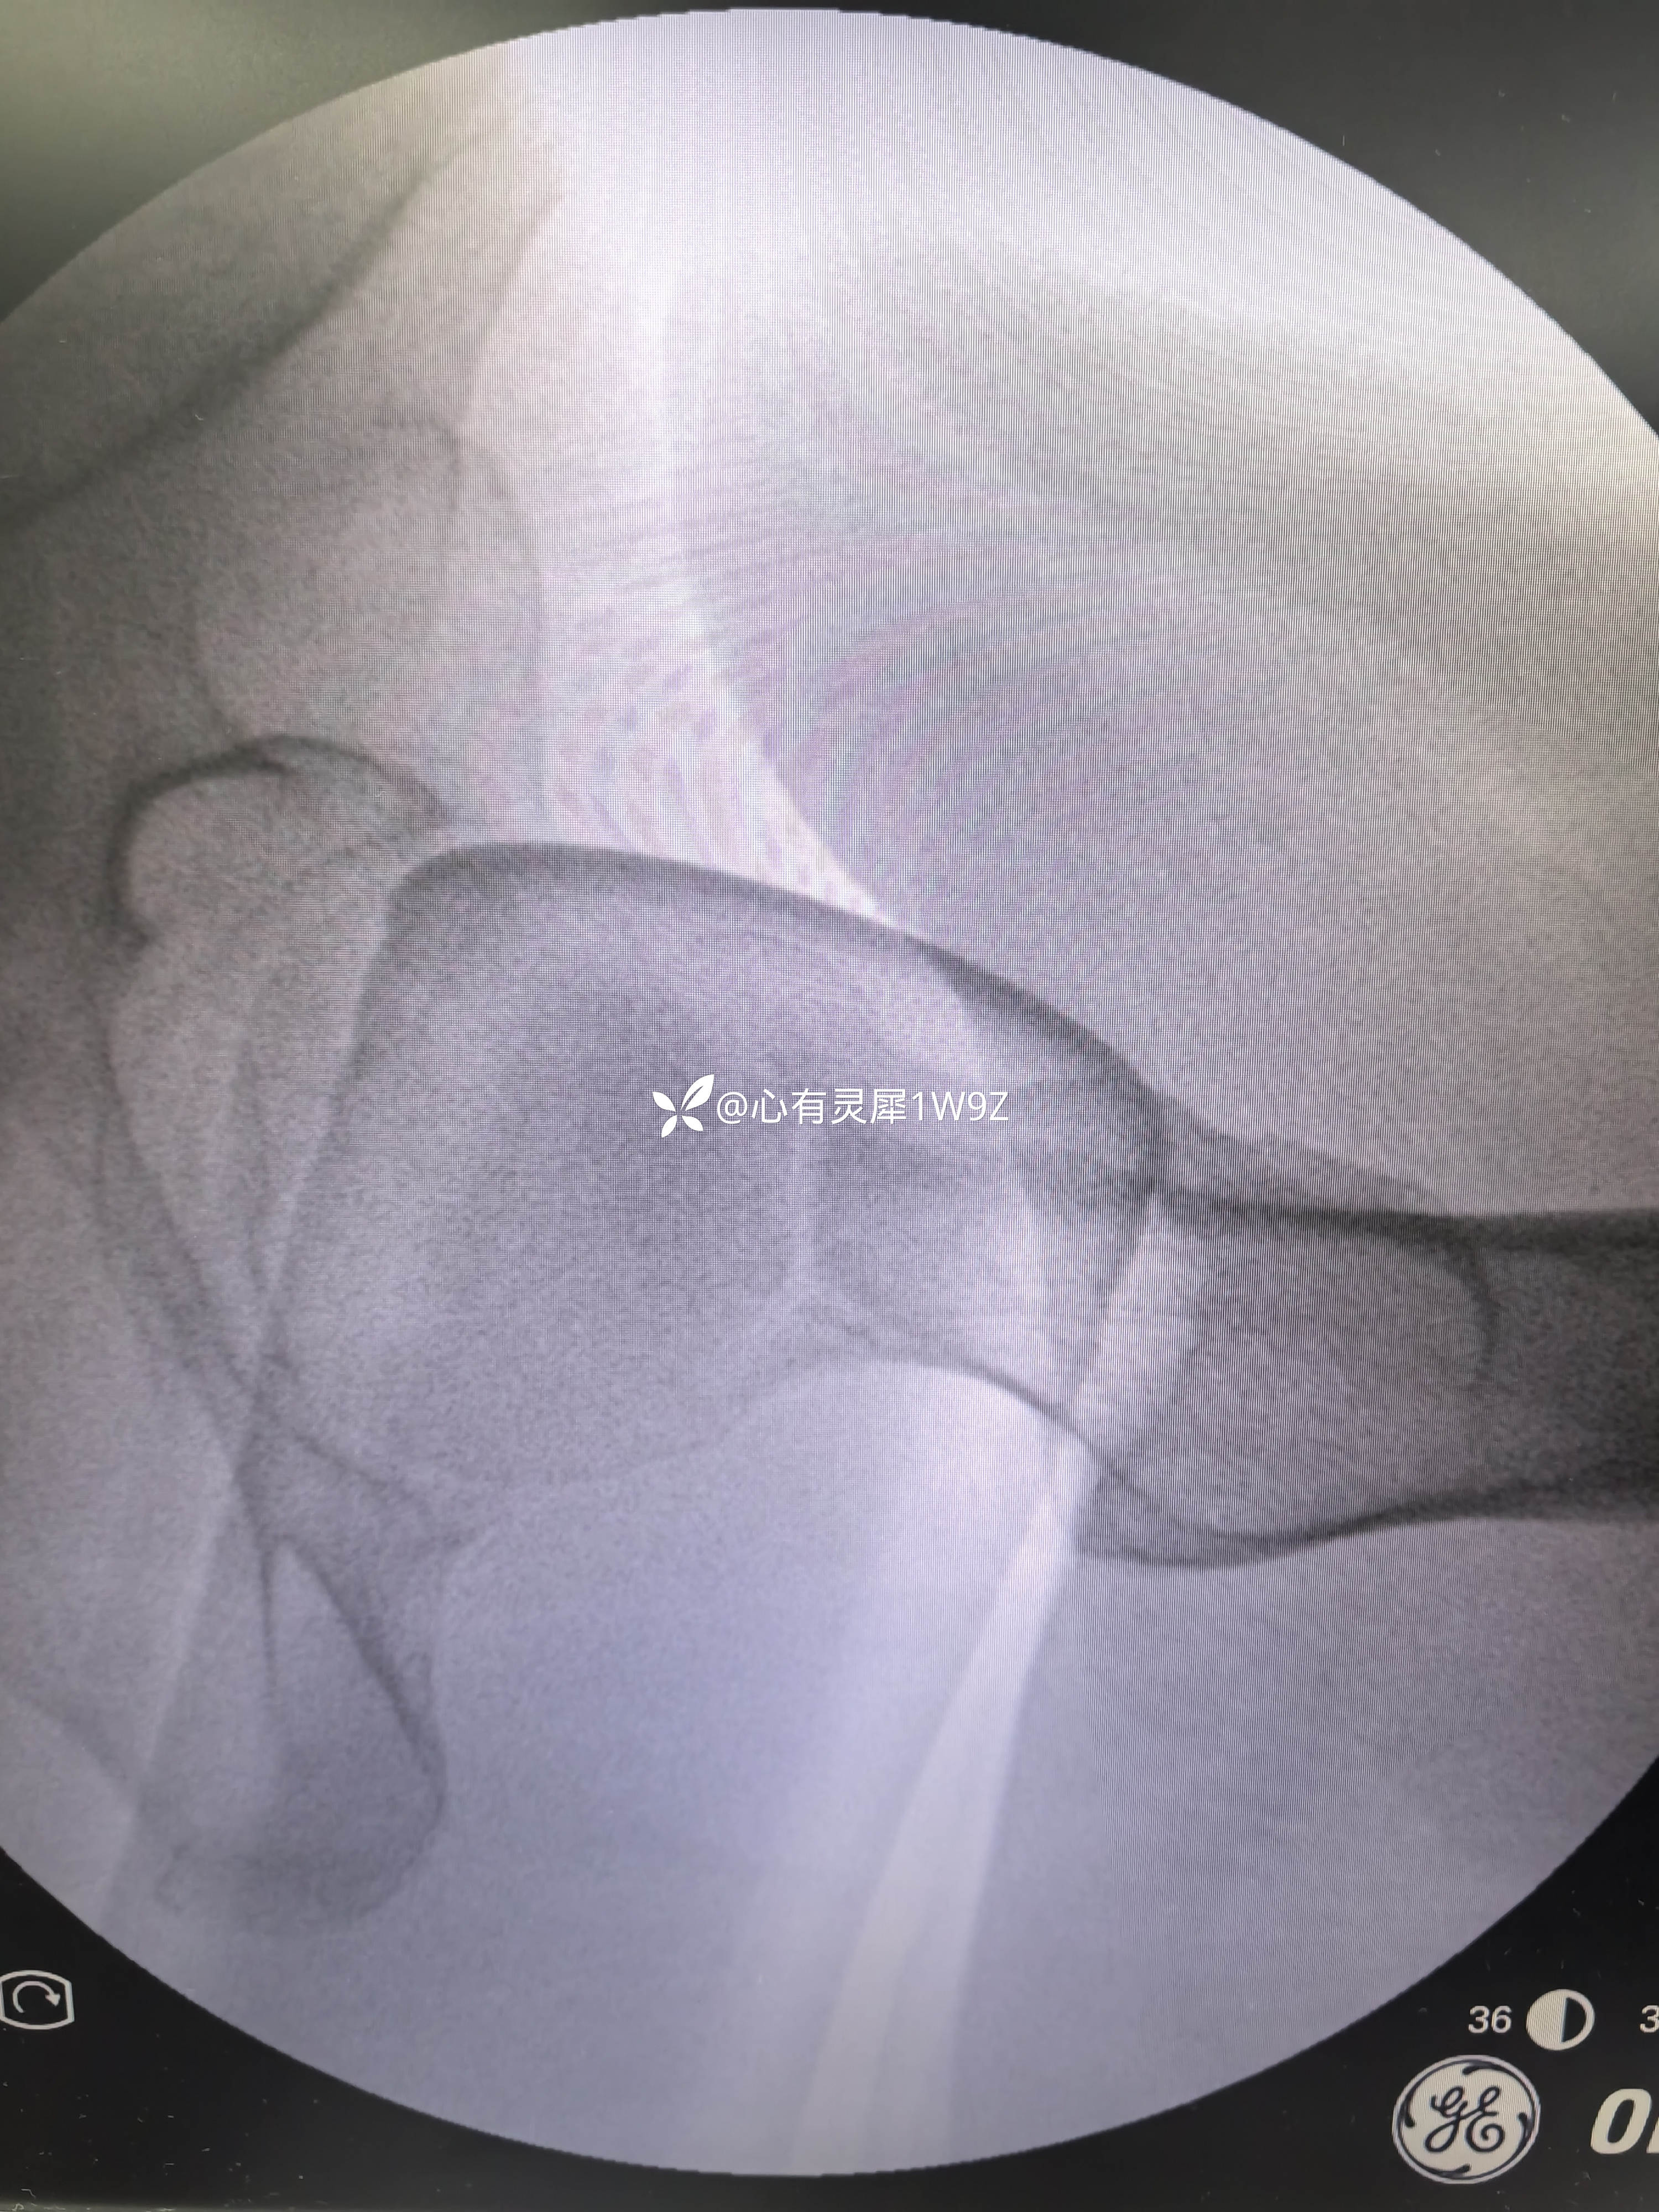

诊断:左侧股骨颈骨折(头下型)garden IV型

2,关于贴壁,平行,长度,角度。自己感觉这次平行和长度都比较满意,贴壁还可以,角度不是很完美,感觉可以接受,就没有再调整。